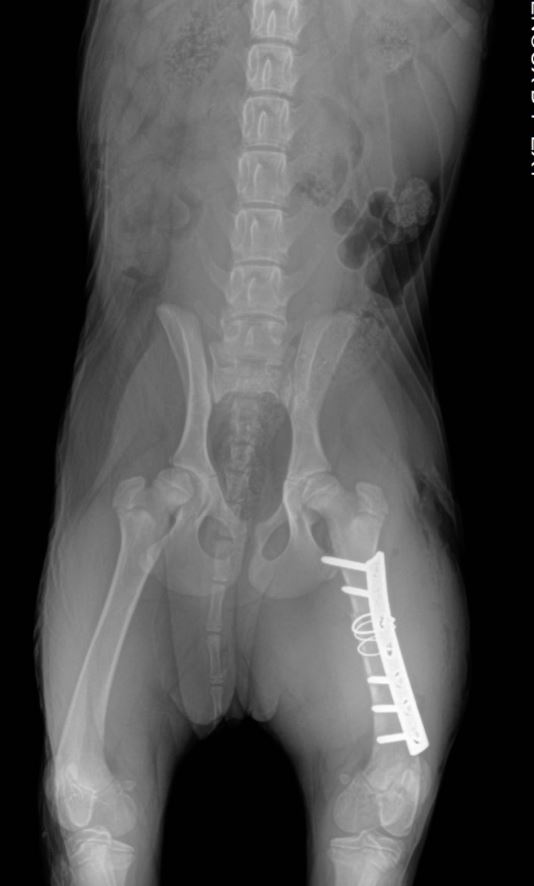

Chirurgies orthopediques:

-réduction des fractures (pose divers implants plaques broches etc),

-rupture du ligament croisé (prothèse ligamentaire)

Pose implant plaque DCP